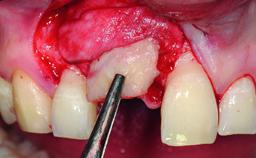

A 32-year-old female Caucasian patient with a compromised maxillary right central incisor was referred to us by a general dentist. Her chief complaints were discomfort and mobility of tooth 11 with unsatisfactory esthetics due to discoloration. The patient reported a previous trauma, some years earlier, as the origin of pathology on the afflicted tooth. Anamnesis was negative for any other dental or periodontal pathology in the remaining dentition. The patient did not take any medication and reported to be a light smoker (5–10 cigs/day). She had high esthetic expectations of her treatment. The extraoral examination revealed a high smile line with full exposure of her maxillary teeth and surrounding soft tissue in the area between the second premolars.

Bone Augmentation Horizontal|Simultaneous|Staged

Augmentation Materials Autogenous chips|Xenogenous|Membrane

Bone Volume Deficient horizontally, requiring prior grafting